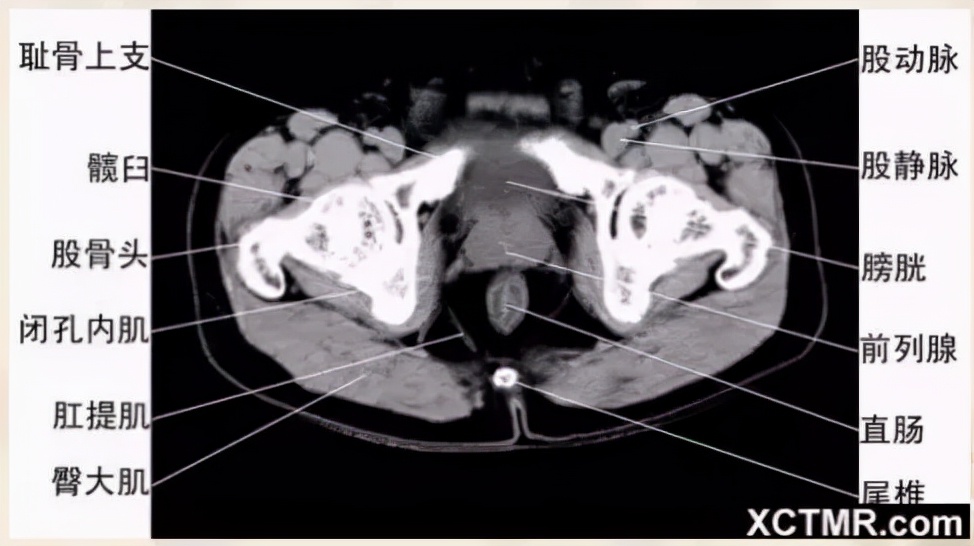

男性盆腔CT断层